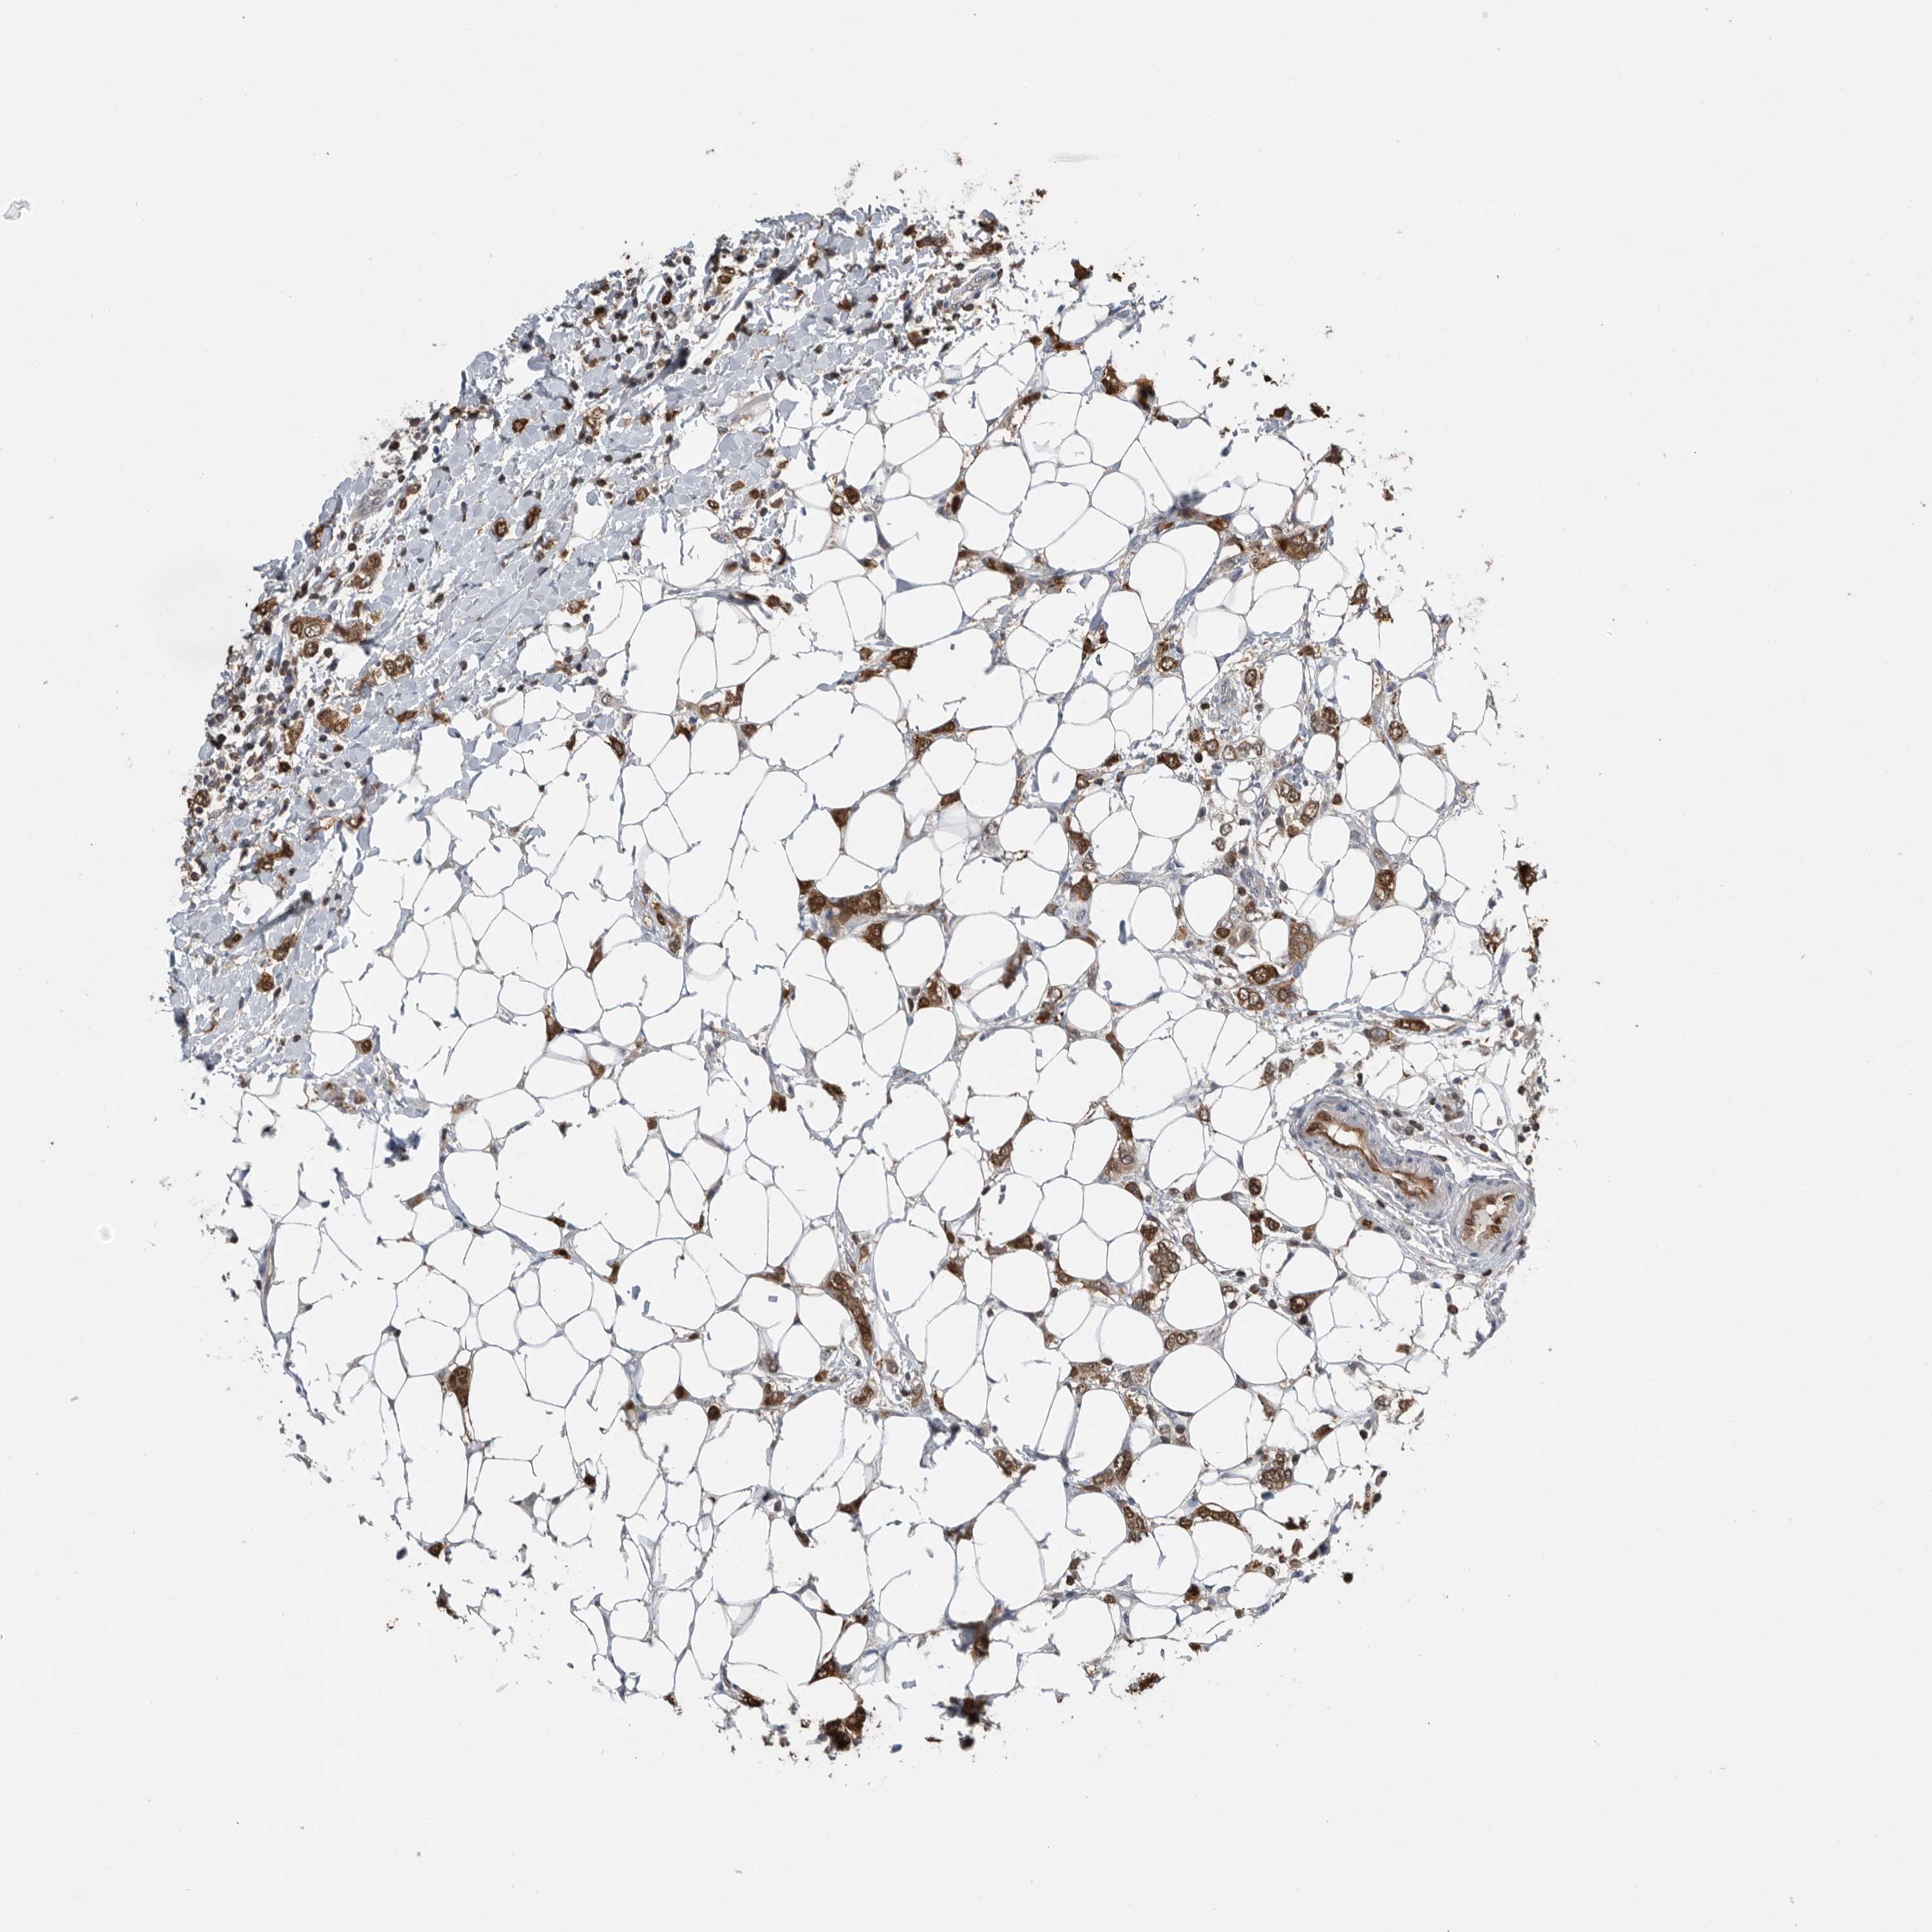

CANCER BREAST CANCER Show tissue menu

BRCA TCGA BRCA VALIDATION PROTEIN EXPRESSION

ANTIBODIES

AND

VALIDATION